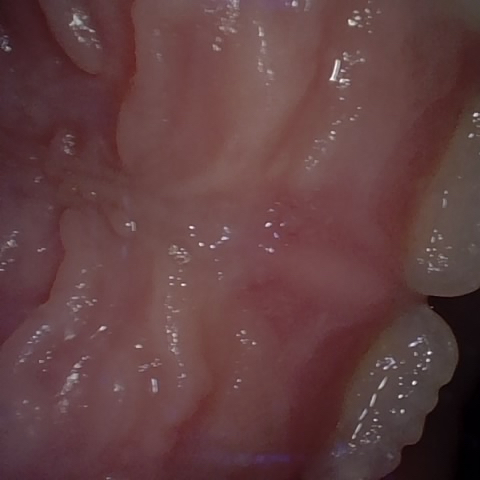

Annotated as "Good"